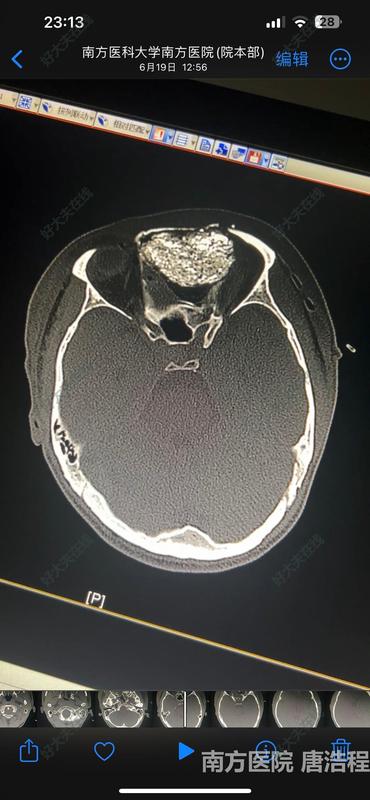

手术设计:考虑患者为青年男性,美容同时兼顾微创,采取发际线线内冠状切口,经额联合鼻内镜下DRAF III联合入路,完成鼻颅底眼眶巨大骨瘤一期完整切除+额骨重建+脑脊液漏修补+前颅底重建手术

手术一期完整切除鼻窦前颅底眼眶巨骨瘤,颅底重建一期愈合,无脑脊液。